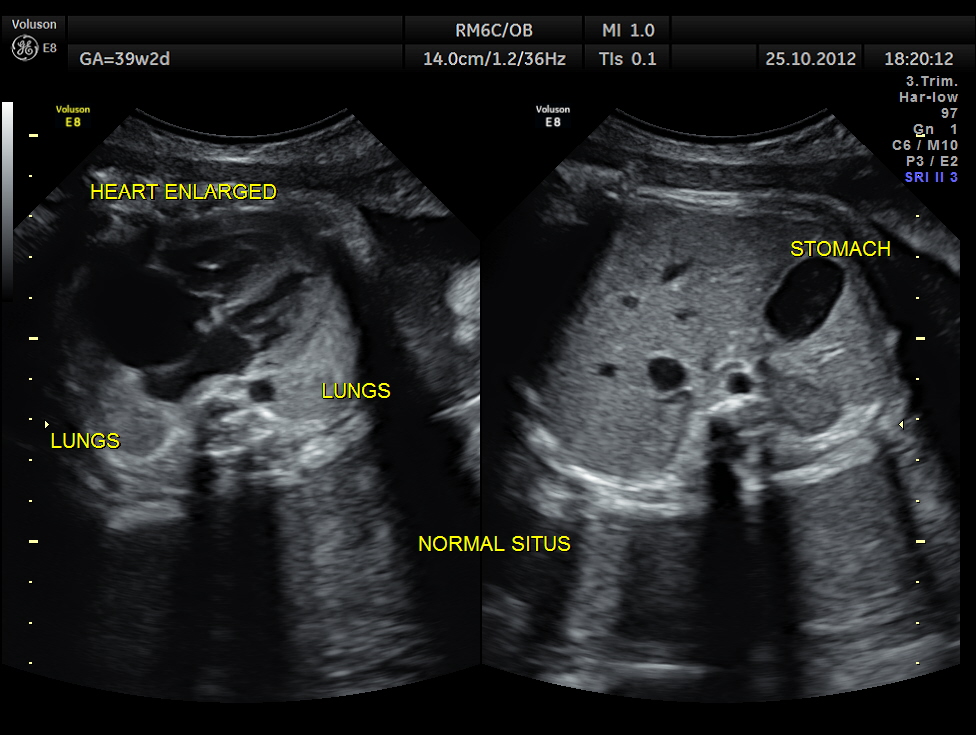

THIS FETUS HAD SEVERE FETAL ANEMIA WITH CARDIAC FAILURE LEADING TO CARDIOMEGALY WITH MITRAL, TRICUSPID AND PULMONARY REGURGITATION .NO OTHER OBVIOUS CARDIAC ANOMALY WAS MADE OUT . THE VENO ATRIAL , ATRIO VENTRICULAR AND VENTRICULO ARTERIAL CONCORDANCE APPEARED TO BE NORMAL; NO SEPTAL DEFECT WAS MADE OUT.

ALL THESE HAVE DEVELOPED WITHIN THE LAST 3 WEEKS .